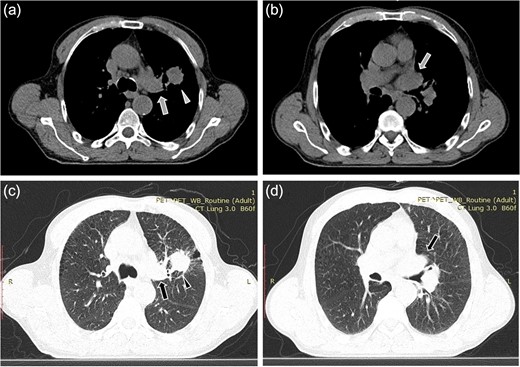

A 61-year-old male, with a history of heavy tobacco abuse presented with dyspnea, left thoracic pain and productive cough. He did not report palpitations or hemoptysis. Chest radiography showed an abnormal shadow in the left upper lung field. Computed tomography (CT) scan revealed a solid lesion of the left upper lobe, 2.9 × 1.8 cm2 in size, with irregular borders (Fig. 1a and c). The tumor seemed to infiltrate the upper left pulmonary vein which appeared dilated and totally occluded due to the presence of thrombotic material in its lumen (Fig. 1b and d). Transthoracic echocardiography showed an intracardiac structure, 4 × 2.5 cm2 in size, protruding from the left pulmonary vein, having no adhesions to the atrial walls. Magnetic resonance imaging (MRI) confirmed the above findings. (Fig 2a–d). A positron emission tomography scan (PET) was also performed. It confirmed the CT findings showing an irregular nodular lesion in the left upper lobe with irregular margins and a diameter of 2.8 cm. It showed a hypermetabolic activity (SUVmax = 29.6) (Fig. 3a and c). It also showed a pleural lesion ventrally to the upper lobe parenchyma. Another hypermetabolic focus (SUVmax = 21.4) appeared in the lumen of the upper lobe pulmonary vein (Fig. 3b and c). Bronchoscopy showed the presence of abnormal tissue in the apicoposterior segmental bronchus of the left upper lobe. Tissue biopsies were obtained but showed no signs of malignancy. Spirometry revealed a mild obstructive pattern. A complete staging work-up, including head CT scan, abdominal ultrasound and whole body bone scintigraphy, did not show any distant metastasis. Based on these the preoperative staging was T4N0M0. Despite failure to obtain a pathologic diagnosis, a surgical treatment including left pneumonectomy with entry in the left atrium and removal of the intracardiac thrombus under cardiopulmonary bypass (CPB) was decided based on the potential immediate life-threatening situation. The presence of such an intracardiac thrombus could be associated with secondary migration, acute blockage of the mitral valve and heart failure, or a distal arterial embolisation resulting into a fatal stroke, a mesenteric ischemia or a severe peripheral ischemia [2, 4]. Median sternotomy was the surgical approach and the patient was cannulated using bicaval venous return and underwent CPB. Left pneumonectomy was carried out, initially with left pulmonary artery ligation and resection, followed by resection of the left pulmonary veins and part of the wall of the left atrium together with the intraatrial mass, which was removed en bloc. The left atrium was sutured closed and then the left main bronchus was resected, completing the left pneumonectomy. The nodal stations 4, 5, 7, 8 and 9 were also sampled. The surgical specimen (Fig. 4) showed the same features as those seen on the CT scan. The patient was successfully extubated directly after the operation and was transferred to the ward on the first postoperative day. The patient was discharged on the 12th postoperative day and received adjuvant chemotherapy thereafter.

Computed tomopgraphy images showing the solid lesion (triangular pointer) with irregular borders in the left upper lobe (a, c). The tumor infiltrates the upper left pulmonary vein (arrow) which appears dilated and totally occluded due to the presence of the thrombus in its lumen (b, d).